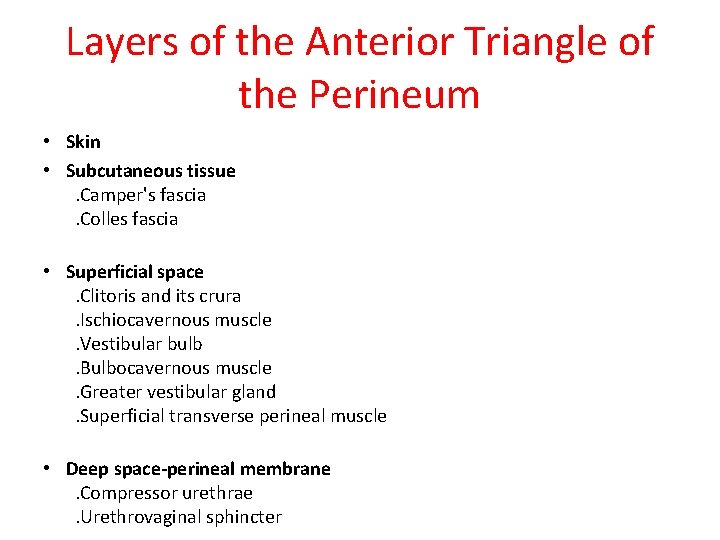

Layers of the Anterior Triangle of the Perineum • Skin • Subcutaneous tissue . Camper's fascia . Colles fascia • Superficial space . Clitoris and its crura . Ischiocavernous muscle . Vestibular bulb . Bulbocavernous muscle . Greater vestibular gland . Superficial transverse perineal muscle • Deep space-perineal membrane . Compressor urethrae . Urethrovaginal sphincter